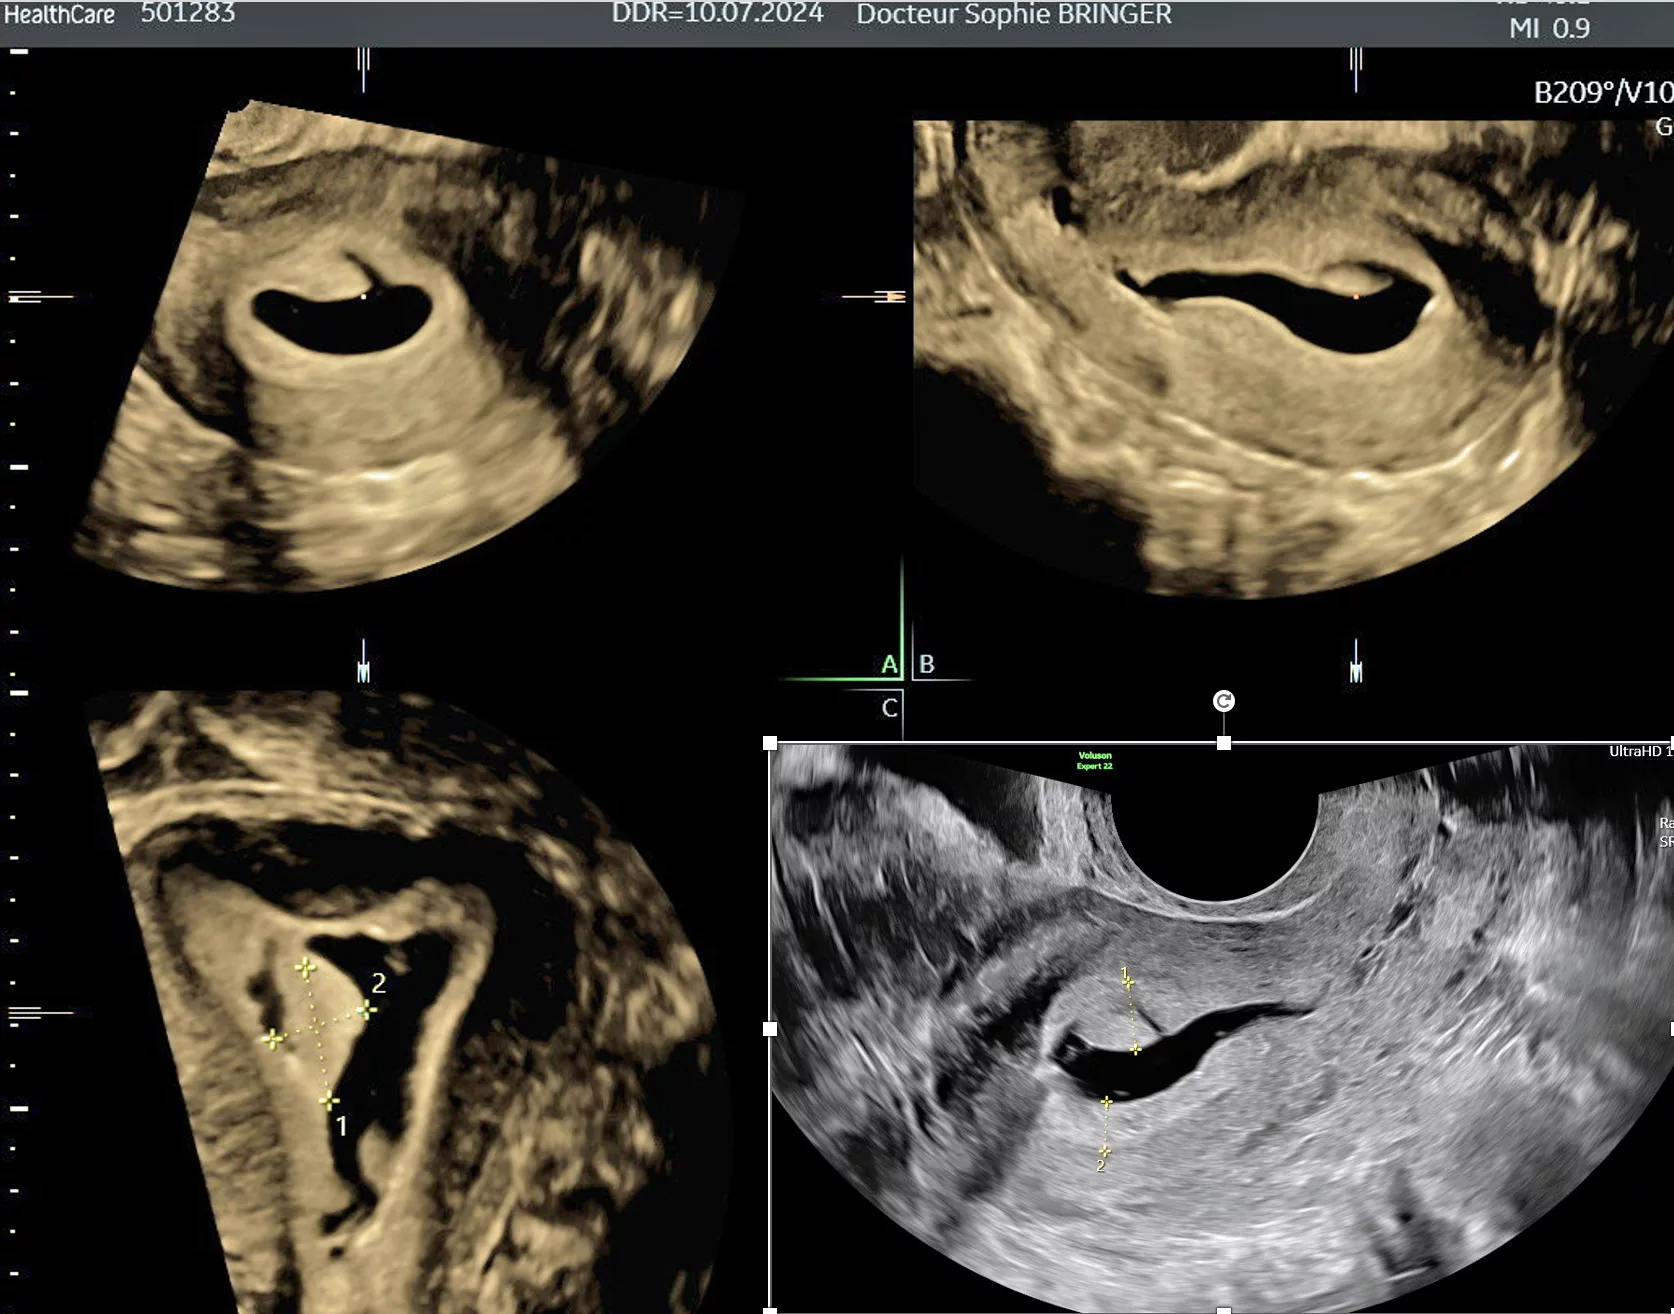

L'Hystérosonographie

Il s’agit d’une échographie pelvienne réalisée par voie endo-vaginale utilisant l’injection de sérum physiologique comme produit de contraste dans la cavité utérine.

Indication de l’examen :

- Bilan d’infertilité

- Diagnostic d’une malformation utérine

- Bilant devant des saignements anormaux

- Bilan de surveillance de l’endomètre

Cet examen est réalisé avant l’ovulation, c’est-à-dire pendant la première moitié du cycle menstruel, après l’arrêt des règles.

Avant de réaliser l’échographie, il est important d’exclure toute grossesse en cours. L’examen ne peut pas s’effectuer s’il y a une infection vaginale ou abdominale.

- Un spéculum stérile en plastique à usage unique est introduit dans le vagin permettant de voir le col utérin après avoir ouvert délicatement les 2 parties du spéculum.

- Le praticien introduit dans le col un petit cathéter en plastique qui permettra d’injecter directement dans l’utérus du sérum physiologique sous contrôle échographique.

- Vous pouvez être sollicité pour la réalisation de l’examen en complément de l’action du praticien.

- Le spéculum est retiré et la sonde d’échographie est introduite dans le vagin. On pratique ensuite l’échographie tout en injectant quelques millilitres de sérum physiologique dans la cavité utérine.

L’examen n’est pas considéré comme douloureux par la plus grande majorité des patientes, mais il est possible de ressentir une gêne au niveau de l’utérus semblable à celle que l’on peut avoir pendant les règles. N’hésitez pas à le signaler au praticien pendant l’examen.